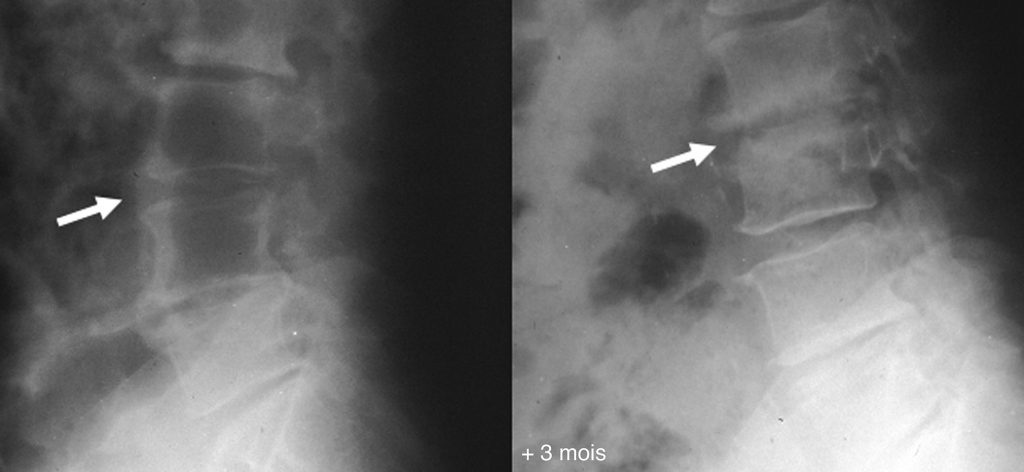

Fig. 78.3 Radiographie de profil du rachis lombaire.

Apparition en 3 mois d’un pincement de l’espace intersomatique en L3-L4 (flèche) avec érosions, irrégularités et aspect flou des plateaux en miroir (flèche).

Source : CERF, CNEBMN, 2022.

- d’érosions, irrégularités, puis de sclérose des plateaux vertébraux ;

- d’un pincement discal : premier signe visible en radiographie, ce pincement est rapide et isolé (figure 78.3) ;